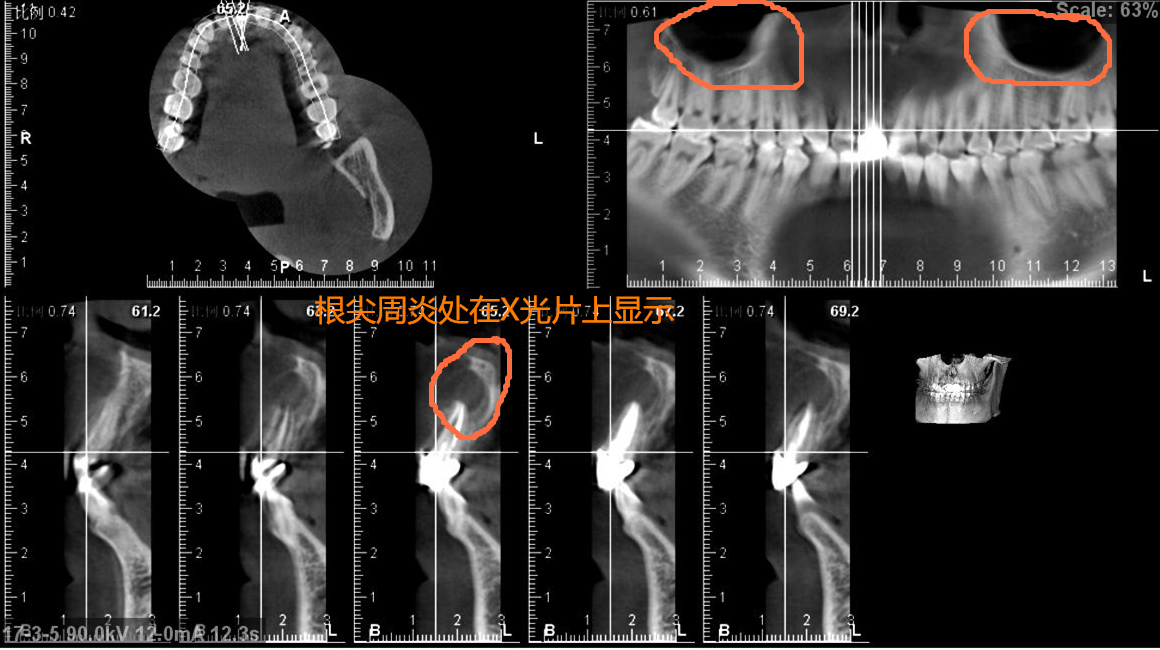

通过检查确诊为右上1根尖囊肿,治疗计划:摘除囊肿植骨恢复。处理措施:局麻切口,翻瓣,摘除囊肿,植入骨粉覆盖骨膜,严密缝合。治疗周期:10天。